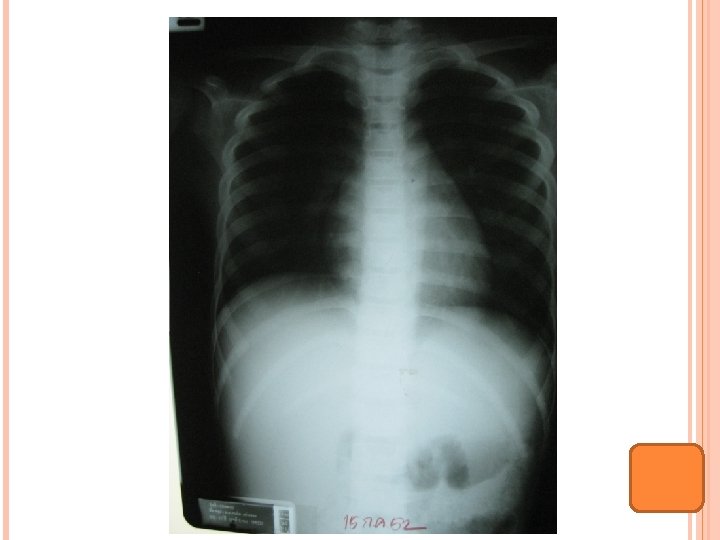

INVESTIGATION 1 เดอนกอน CBC: Hct 28. 6%, Hb 9 g/dl, corrected WBC 9, 600, N 37%, L 43%, M 18%, NRC 153/100 WBC, plt 117, 000 MCV 72. 9, MCH 22. 9, MCHC 31. 4, RDW 20. 8 ESR 82 mm/hr, ANA-, ASO positive 1: 1, RF -, CRP + 1: 64, Melioid titer 1: 40, H/C no growth, PPD CXR: mild cardiomegaly EKG: NSR, HR 120/min, QRS axis 750, PR 0. 12 sec, QTc 0. 38 sec, borderline LVH Echocardiogram: EF 76. 8%, mild LV enlargement, trivial MR

BMA: inadequate BM biopsy: fragment of cartilage, no bone marrow tissue seen Film bone survey: multiloculated cystic lesion at distal of Lt femur, no osteolytic lesion, suspected benign condition, No malignancy condition Bone scan: ? Ultrasound abdomen: hepatomegaly